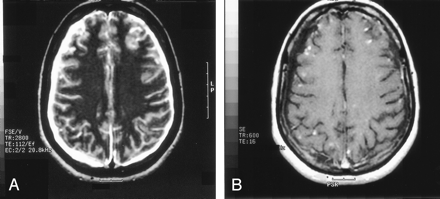

On the dermatologic examination, diffuse asymptomatic papules were found, mostly in the lower limbs. These lesions had a diameter of a few millimeters, were surrounded by a erythematous rim, and their color was pink, with a central atrophic area characterized by adherent whitish desquamation (Fig 1); a skin biopsy on the leg confirmed the diagnosis of Degos disease (Fig 2). The neurologic examination noted anisocoria, hearing loss on the left side, diffuse muscle hypotrophy, impaired finger movements, mild paresis of the right arm, paralysis of both legs, symmetrically reduced muscular reflexes, hypoesthesia, hypopallesthesia of the lower limbs, constipation, and urinary incontinence. No fever or meningeal signs were present. Brain MR imaging (Figs 3–5) showed both old and new ischemic lesions, mainly present in the left hemisphere, and numerous small nodules, localized in both the cerebral and the cerebellar cortices. A diffuse and homogeneous thickening of the meninges, with some subdural fluid accumulation, was also evident in the frontoparietal region. Ependymal enhancement was noted in the atrium of the right lateral ventricle. Hydrocephalus and venous thromboses were ruled out. Spinal MR imaging showed thinning of the spinal cord, with mild alteration of the signal intensity in the thoracic cord (Fig 6). A subtle, focal cord enhancement was found in the cervical and thoracic cord (Fig 7).

Contrast-enhanced T1 axial images show multiple nodular lesions located in the peripheral gray, subarachnoid spaces and leptomeninges, with diffuse dural enhancement. Note the ependymal enhancement (A) of the right atrium and a small infarct in the left caudate head.

T2 (A) and T1 (B, contrast-enhanced) axial images at supraventricular level show right thickened meninges, subdural CSF collection (right side more evident than left) and multiple superficial lesions.